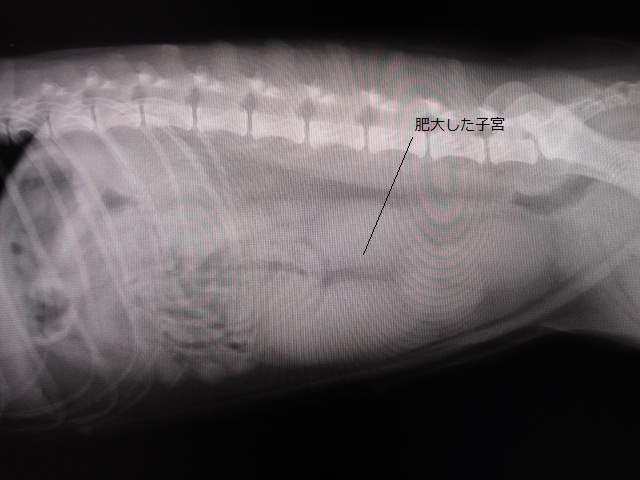

術前レントゲン

術前のレントゲンです。

明らかに子宮が肥大しています。